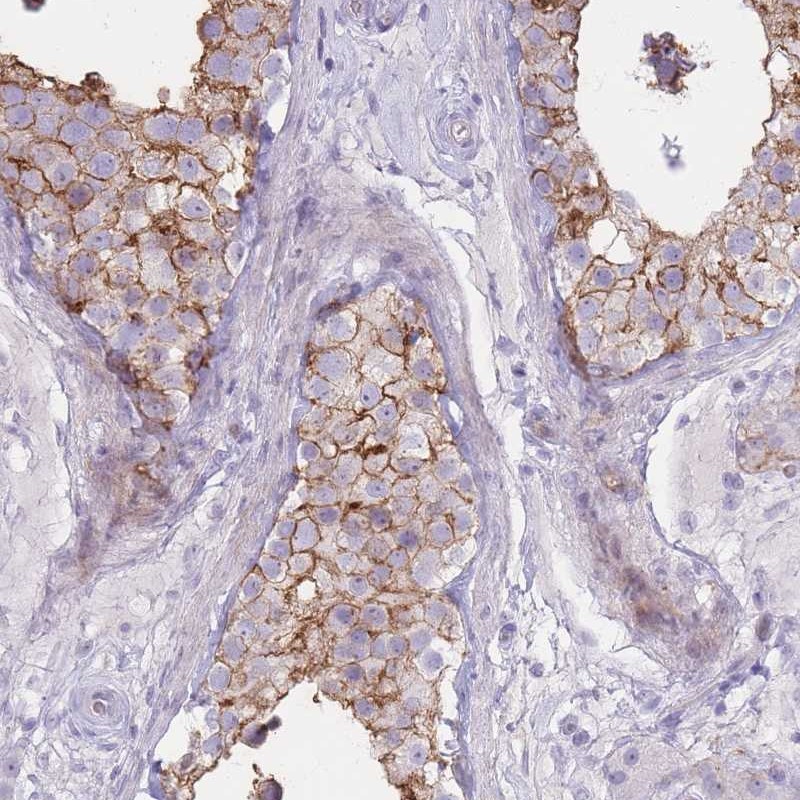

Immunohistochemical staining of human testis shows strong cytoplasmic and membranous positivity in cells in seminiferus ducts.